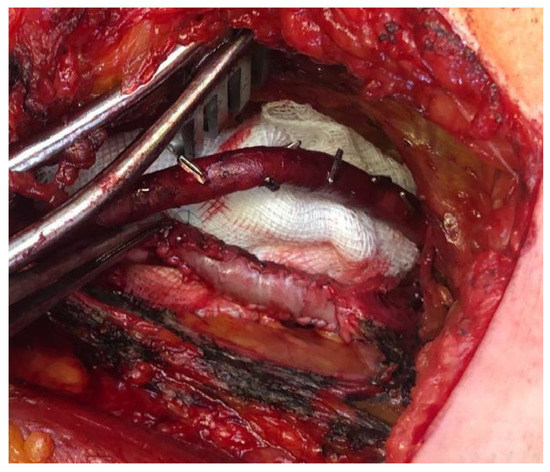

Intraoperative findings confirmed the presence of 6/4 saccular aneurysm located along the distal popliteal vein (Figure 3).

Figure 3.

Intraoperative view after the isolation, incision and drainage of the popliteal vein aneurysm.

The popliteal vein and the aneurysm were isolated, followed by longitudinal incision and drainage of the aneurysm, which revealed no thrombotic material. Next, the surgical procedure consisted of tangential aneurysmectomy followed by patch angioplasty with bovine pericardium (Figure 4).

Figure 4.

Tangential aneurysmectomy of the PVA and patch angioplasty with bovine pericardium.